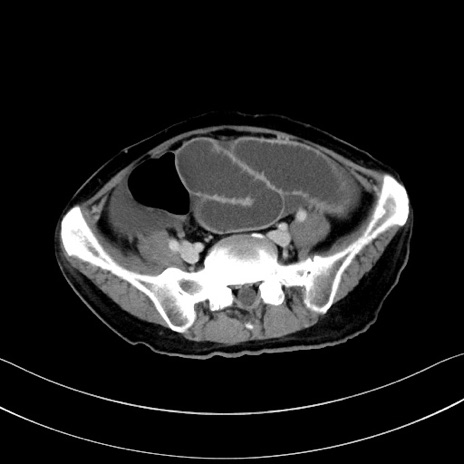

冠状断像

【症例】60歳代男性

【主訴】嘔吐

【現病歴】胃癌にて胃全摘後。食思不振が悪化し、夜中に嘔吐することがある。

【既往歴】胃癌、胃全摘、脾摘、胆摘後

【データ】WBC 5900、CRP 10.56